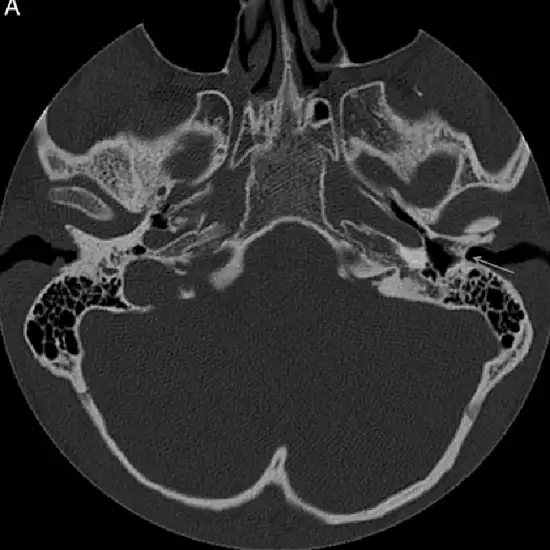

NCCT (Non-Contrast computed tomography) temporal axial and coronal is an imaging procedure. The scan focus on the different views of lower skulls and their surrounding tissues. The procedure is prescribed to patients with hearing loss problems, persisting ear infections, and diseases of both the middle and inner ear. For the best and most suitable study of the temporal bone, the doctor recommends this scan.

3. To diagnose cholesteatoma which is an abnormal growth of skin in the middle ear behind the eardrum.